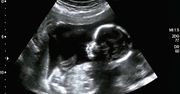

Kiedy kobieta dowiaduje się, że zostanie matką, na świecie nie ma dla niej nic ważniejszego niż dziecko. Jednak kiedy emocje nieco opadną, zaczynają pojawiać się problemy. Bardzo dużo słyszy się o tym, że pracodawcy po prostu nie chcą współpracować z ciężarnymi. Kobiety, które tracą pracę w czasie ciąży, bardzo często mają problem ze znalezieniem nowej posady. Dlatego wiele młodych kobiet, które zachodzą w ciążę boją się, że stracą pracę. Okazuje się, że w show biznesie przyszłe mamy spotykają się takimi samymi problemami. Dowiedz się, które polskie gwiazdy straciły pracę przez ciążę. Zobacz także: Napisała antyporadnik dla matek. Szokuje nie tylko na okładce